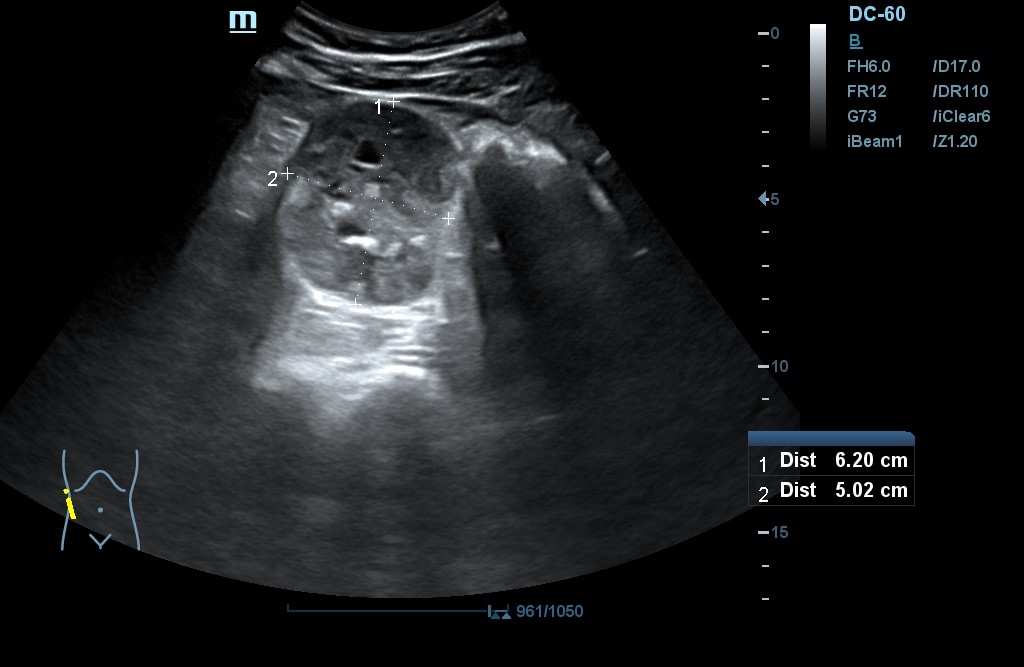

- POCUS: Lesión en polo inferior de riñón derecho (RD) de 6,2 x 5,02 cm de diámetro, con neovascularización y zonas hiperecogénicas. No signos de hidronefrosis. Disminución del flujo venoso con Doppler pulsado. Resultados compatibles con masa renal sólida a filiar. RI sin alteraciones. Jets vesicales presentes. Próstata de contornos regulares y ecogenicidad homogénea. Volumen prostático de 44 cm3.

- Concordancia con el hospital: se realiza un TAC abdominal que determina masa sólida exofítica en polo inferior RD con amplia necrosis central, calcificaciones y neovascularización. Mide 6,8 x 5,5 cm. pT3a N0M0.